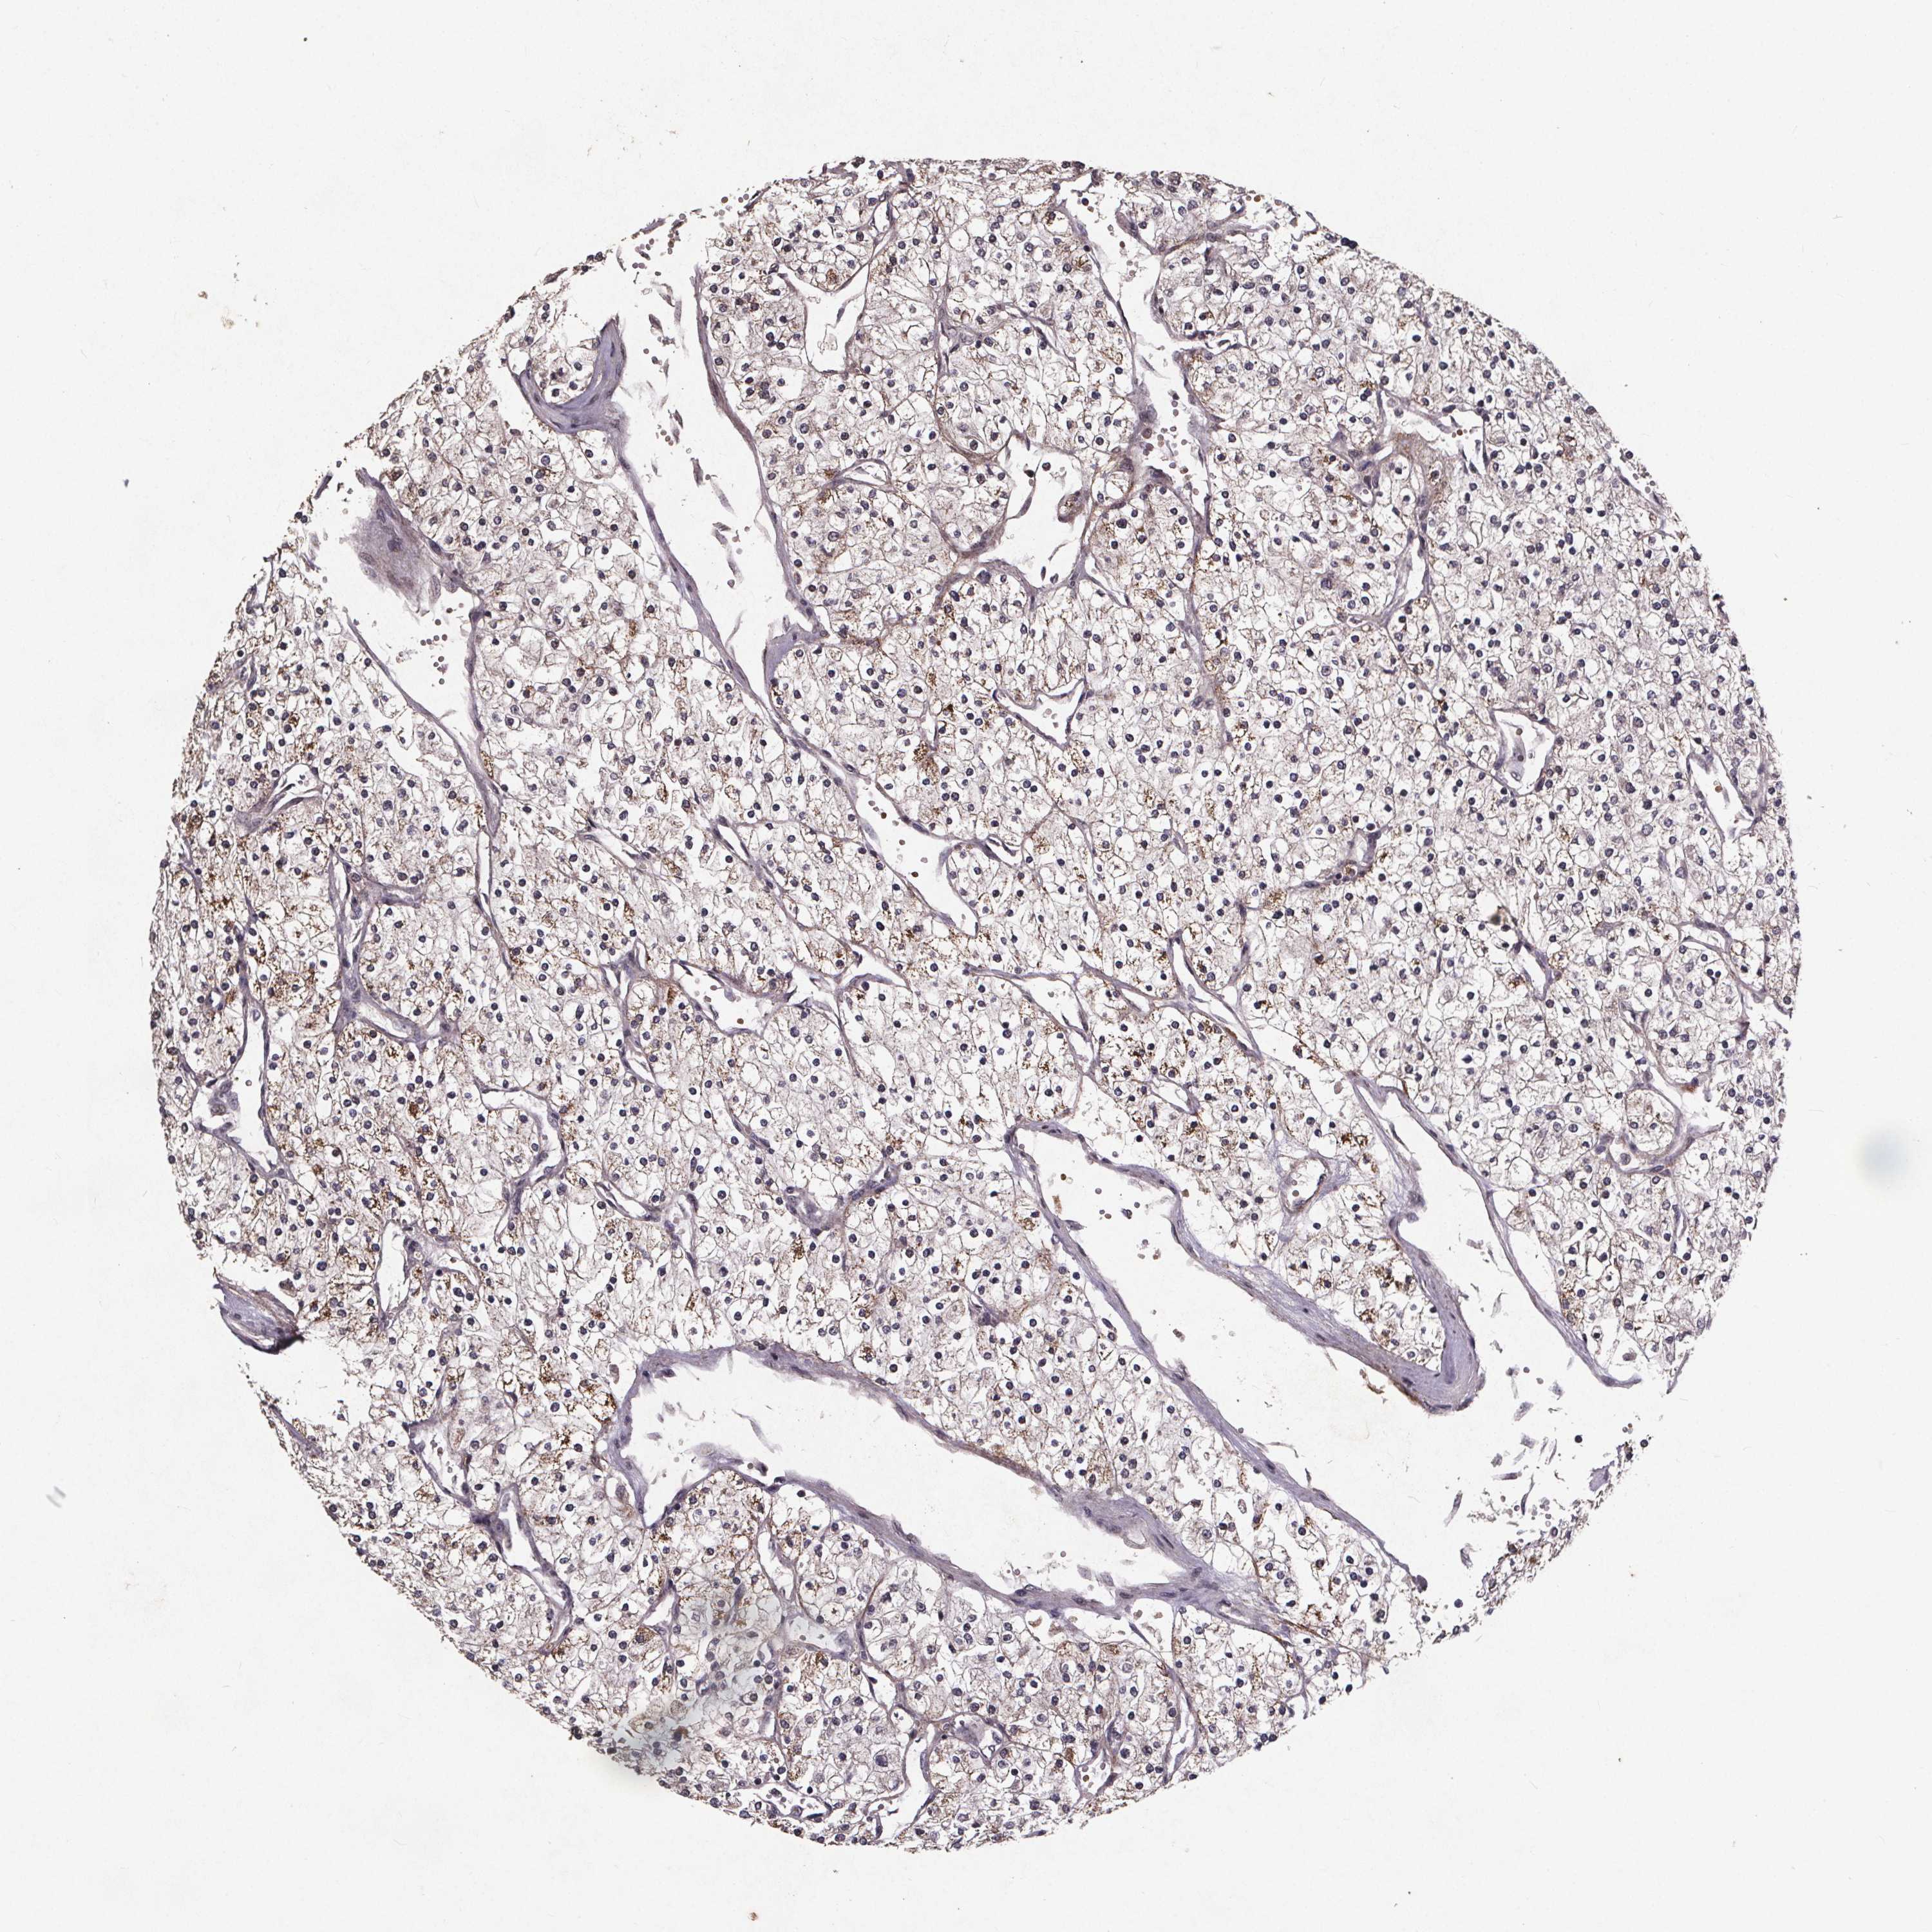

KIDNEY RENAL CLEAR CELL CARCINOMA (VALIDATION) - Interactive survival scatter ploti

The Survival Scatter plot shows the clinical status (i.e. dead or alive) for all individuals in the patient cohort, based on the same data that underlies the corresponding Kaplan-Meier plots. Patients that are alive at last time for follow-up are shown in blue and patients who have died during the study are shown in red.

The x-axis shows the expression levels (FPKM) of the investigated gene in the tumor tissue at the time of diagnosis. The y-axis shows the follow-up time after diagnosis (years). Both axes are complimented with kernel density curves demonstrating the data density over the axes. The top density plot shows the expression levels (FPKM) distribution among dead (red) and alive patients (blue). The right density plot shows the data density of the survived years of dead patients with high and low expression levels respectively, stratified using the cutoff indicated by the vertical dashed line through the Survival Scatter plot. This cutoff is automatically defined based on the FPKM cutoff that minimizes the p-score. The cutoff can be changed by dragging the vertical line or by entering a cutoff value in the square labeled "Current cut-off".

Under the Survival Scatter plot the p-score landscape (black curve; left axis) is shown together with dead median separation (red curve; right axis). Dead median separation is the difference in median mRNA expression between patients who have died with high and low expression, respectively. It is calculated as follows: median FPKM expression of dead patients with high expression - median FPKM expression of dead patients with low expression. This is intended to aid the user in visually exploring custom cutoffs and the associated p-scores and dead median separation.

Individual patient data is displayed and can be filtered by clicking on one or more of the category buttons on the top of the page. Categories describing expression level and patient information include: high, low, alive, dead, female, male and tumor stages. The scale of the x-axis can be toggled between linear and log-scale by clicking on the "x log" button. Mouse-over function shows TCGA ID, patient information and mRNA expression (FPKM) for each patient.

& Survival analysisi

Kaplan-Meier plots summarize results from analysis of correlation between mRNA expression level and patient survival. Patients were divided based on level of expression into one of the two groups "low" (under cut off) or "high" (over cut off). X-axis shows time for survival (years) and y-axis shows the probability of survival, where 1.0 corresponds to 100 percent.

GPX3 is not prognostic in Kidney Renal Clear Cell Carcinoma (validation)

Best expression cut offi

Based on the FPKM value of each gene, patients were classified into two groups and association between prognosis (survival) and gene expression (FPKM) was examined. The best expression cut-off refers the FPKM value that yields maximal difference with regard to survival between the two groups at the lowest log-rank P-value. Best expression cut-off was selected based on survival analysis .

When clicking on this number, the vertical dashed line indicating cut-off, the interactive survival plot, and the Kaplan-Meier curve will be adjusted to show results based on the best expression cut-off.

: 2748.47

P scorei

Log-rank P value for Kaplan-Meier plot showing results from analysis of correlation between mRNA expression level and patient survival.

N/A

TCGA RNA samplesi

RNA-seq data is reported as average FPKM (number Fragments Per Kilobase of exon per Million reads), generated by the The Cancer Genome Atlas (TCGA) .

Normal distribution across the dataset is visualized with box plots, shown as median and 25th and 75th percentiles. Points are displayed as outliers if they are above or below 1.5 times the interquartile range. FPKM values of the individual samples are presented next to the box plot.

Average pTPM 2058.1

Number of samples 100